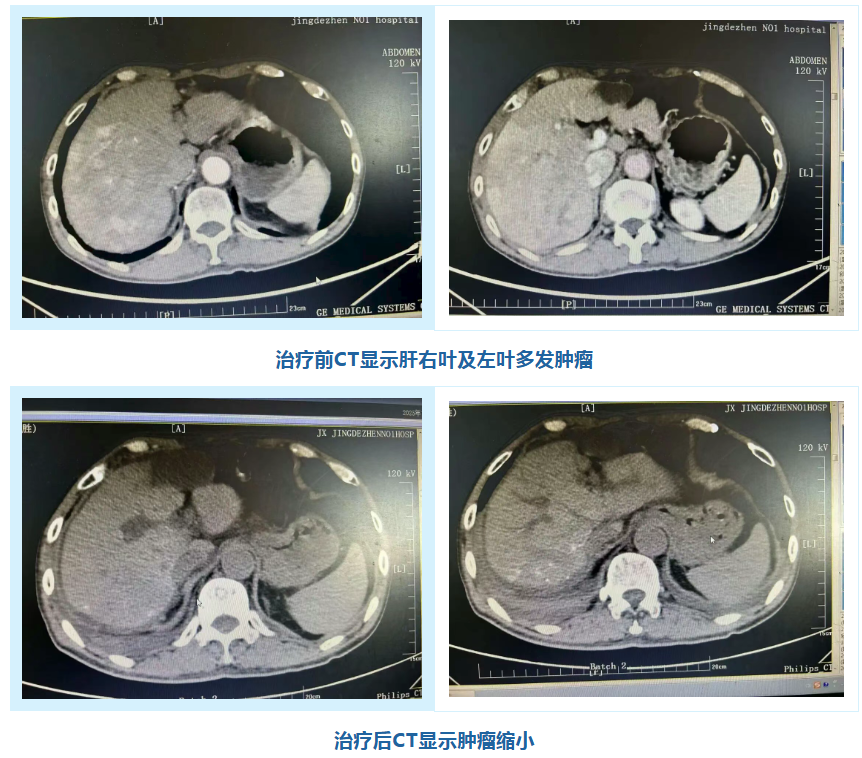

学成归来后,胡海中医师迅速将所学技术应用于临床。本例接受微创手术治疗的患者为老年男性,肝恶性肿瘤术后5月余,复查时发现甲胎蛋白显著升高,增强CT提示肝右叶及左叶多发占位,通过详细检查后,诊断为原发性肝细胞癌(CNLC分期 IIb期)。经科室充分讨论,并与患者及家属深入沟通后,决定为其施行TACE+HAIC联合治疗方案。前者通过将栓塞剂注入肿瘤的供血动脉,阻断肿瘤的血液供应,使肿瘤细胞因缺血、缺氧而发生坏死、凋亡,从而抑制肿瘤的生长和扩散,后者在TACE的基础上减少化疗药物在外周血中的分布,从而降低化疗药物的全身副作用。

微创手术过程顺利,历时约45分钟,患者的甲胎蛋白(AFP)从治疗前的31886ng/ml降至治疗后的7.94ng/ml(正常值为0-7ng/ml)。该技术的核心与难点在于精准栓塞肿瘤的供血动脉,同时最大限度地保护正常的肝功能。其显著优势在于创伤微小、恢复较快,特别适用于肿瘤较大、位置特殊或者患者身体状况较差,无法进行手术切除的中期肝癌患者,通过TACE治疗,可以控制肿瘤的生长速度,缩小肿瘤体积,改善患者的症状,延长患者的生存期。